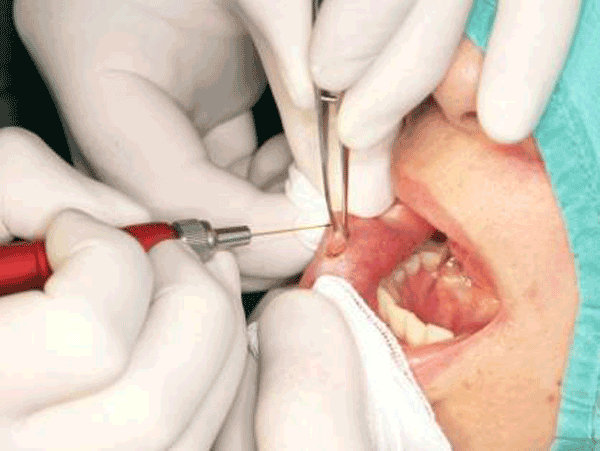

Tobacco Use

Smoking and tobacco products contribute to gum diseases like periodontitis, tooth discoloration, and bad breath. Nicotine reduces blood flow to the gums, weakening the oral immune system and causing serious dental issues.